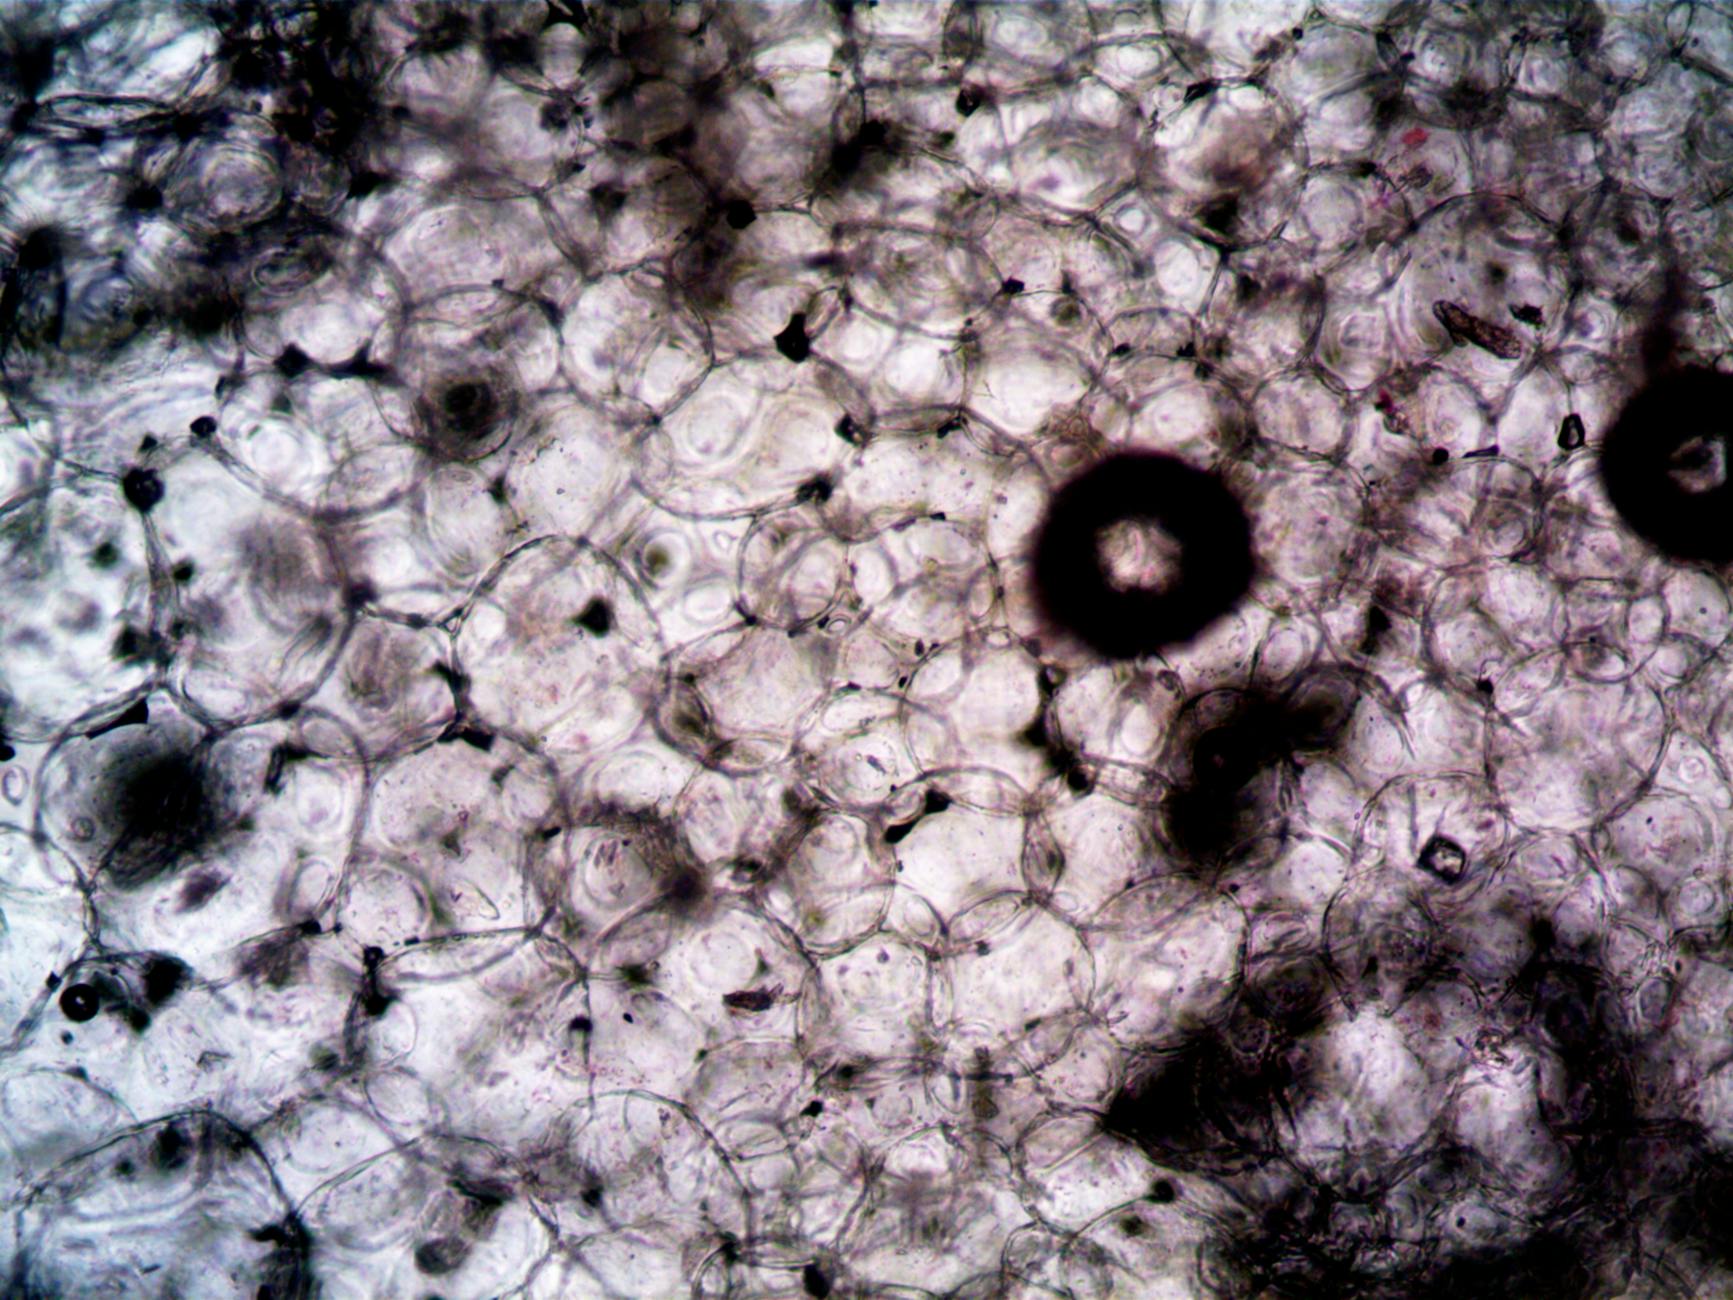

Adipose-derived stem cells restore scarred skin by releasing molecules that reactivate the fibroblasts—the cells responsible for producing collagen and elastin—that become dormant or damaged during acne inflammation. When injected into scar tissue, ADSCs don’t simply transform into new skin cells. Instead, they function as “repair coordinators,” stimulating three critical healing processes: increased collagen synthesis (the structural rebuilding), angiogenesis (formation of new blood vessels to improve circulation and skin quality), and fibroblast migration (repopulation of damaged areas with collagen-producing cells). ADSCs can also differentiate into fibroblasts themselves, directly increasing collagen and elastin density in treated skin over weeks and months.

A key mechanism that emerges from recent research is the cells’ ability to suppress the NLRP3 inflammasome pathway—a cellular trigger for chronic inflammation. Acne scars persist partly because inflammatory signals remain active in the tissue, preventing normal healing. By dampening this inflammatory environment, ADSCs allow the skin to transition from a damaged state into active regeneration. This explains why results often continue improving for months after treatment: the initial injection sets off a cascade of biological repair that unfolds gradually as collagen remodels and new blood vessels establish themselves. This differs fundamentally from laser resurfacing, which relies on controlled damage to stimulate healing; stem cells work *with* the body’s natural repair mechanisms rather than forcing them through trauma.